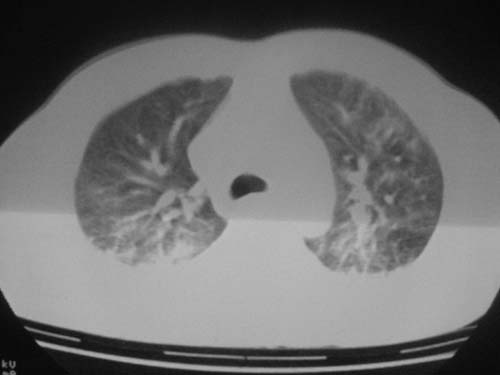

这是第五天拍的ct,纵隔窗我没都传,实在是太费时,请教各位老师,此病人有肺水肿吗?帮忙分析一下